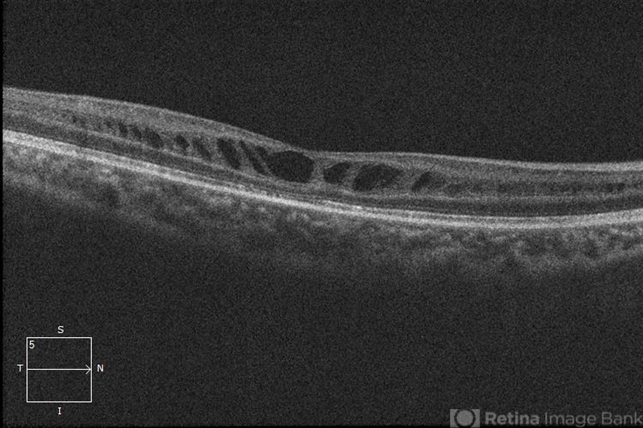

- retinoschisis, retinal hole

Optical coherence tomography system

Zeiss Cirrus 5000 - Description

- 21-year-old male with congenital retinoschisis with bilateral macular involvement and large inner retinal hole OD.